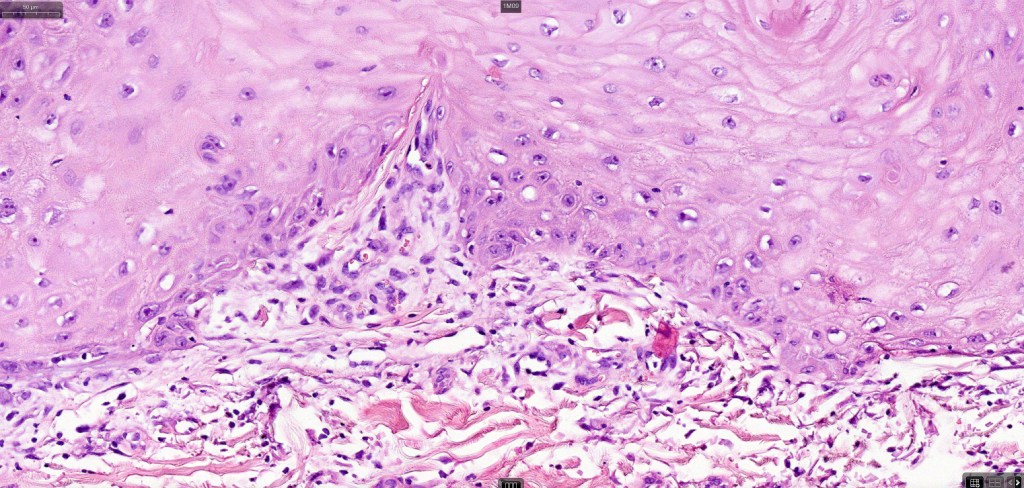

•Keratoacathoma (nowdays regarded as a variant of well differentiated squamous carcinoma) is characterized by a crateriform squamous epithelial lesion (dilated follicular infundibulum) with central keratin plug and adjacent collarette extending to the mid-dermis

•Well differentiated squamous epithelium often with a characteristic ground-glass appearance

•Only mild pleomorphism & basally located mitoses

Below is a fascinating case shared on McKee Derm by Dr. James Simpson. There is an obvious keratoacanthoma but at the edge of the lesion there is marked atypia with nuclear enlargement and pleomorphism. This is also evident in the adjacent epidermis and in the deeper nests.